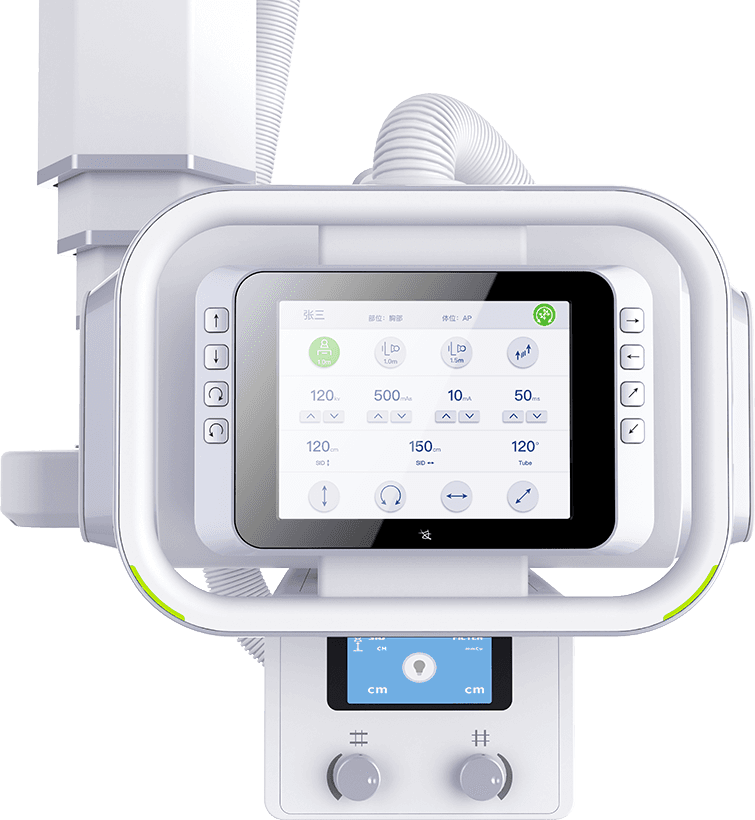

智能触控大屏

液晶触摸屏,触摸操控设备运动,实时调整各类检查参数,

并同步显示患者信息、曝光参数及摆位提示。 -

任意键制动

一键切换运动过程中,任意键可停止设备运动,

保障运行状态安全可靠 -

任意键唤醒

自定义设置待机时长,任意键唤醒,环保节能; -

智慧剂量控制

自动曝光控制(AEC)功能,提升摄片影像质量同时

有效降低摄片剂量,提升检查效率。 -

限束器智能缩窗

根据不同部位自动设置照射野,减少散射线及不必要的X光剂量,

提升影像质量。